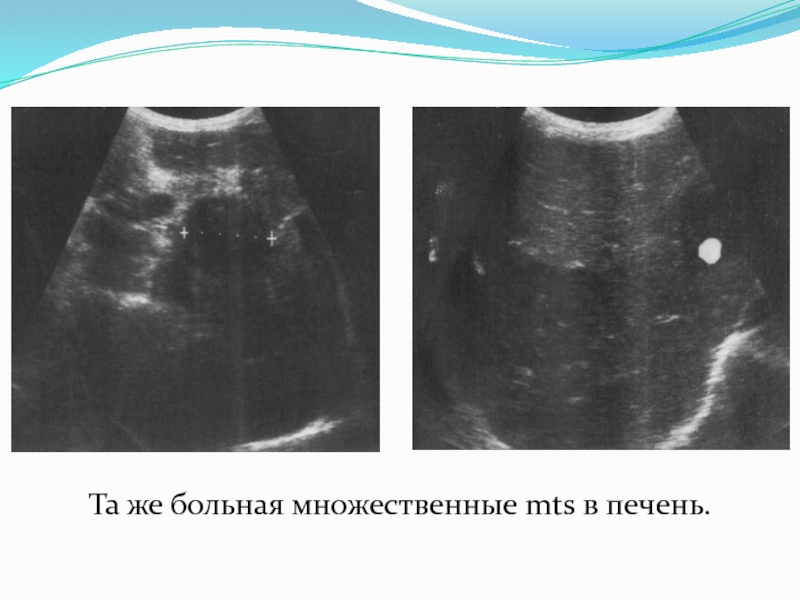

Метастатические поражения печени в ультразвуковом изображении характеризуются